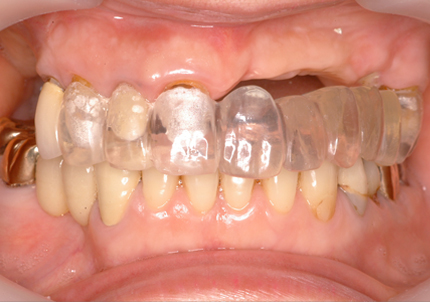

5.仮歯装着歯装着

6.インプラントシリンダーテック作製

7.最終補綴作製(前歯部アバットメント装着)

8.ジルコニアフレーム、アバットメント試適

9.セラミック焼成

10.上顎補綴物装着(2008年12月)

12.上顎補綴物装着(2009年5月)